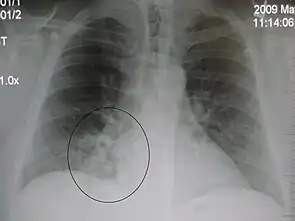

Right upper lobe pneumonia as marked by the circle.